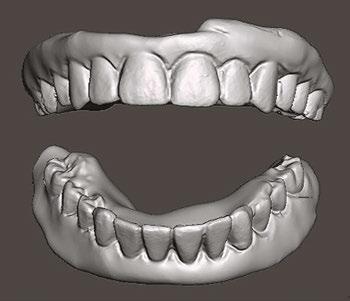

A CBCT scan was taken and panoramic views of the maxilla and mandible evaluated (Figure 3). Bilateral pneumatization of the maxillary sinus was noted, but adequate bone height was present between the premolars for implant placement to support an All-on-X hybrid prosthesis. In the mandibular arch, sufficient height was available between the mental foramen bilaterally and over the inferior alveolar nerve for implant placement to also sup port an All-on-X fixed hybrid prosthesis. A discussion was held with the patient that implants could be placed in both arches that would allow restoration with fixed prosthetics. Should sufficient insertion torque be achieved at the time of implant placement, a screw-retained hybrid provisional prosthesis would be placed and worn for several months during healing after which a final prosthesis would be fabricated. The patient would also be able to do a “trial-run” of the esthetics with the provisional prosthesis, with any requested modifications made when the final prosthesis was designed and fabricated. The treatment plan included six implants in each arch to support the planned hybrid prosthe ses. The patient was informed that reduction of the crestal bone would be required to achieve a flat ridge for adaptation of the prosthesis to the ridge as well as to provide adequate interarch space for the final prosthesis. The patient accepted the treatment plan. An intraoral scan of the arches was performed with Medit i500 (Medit Corp, Seoul, Korea) as well as the current complete arch maxillary and mandibular dentures (Figure 4). The patient was dismissed and scheduled for the surgical appointment.

(Figure 10). The planned provisional hybrid prostheses were evaluated for esthetics and alignment of the midline in relation to the arches. The flange area was modified to convert the virtual prosthesis from a denture to a hybrid prosthesis (Figure 11). The virtual designed provisional hybrid prostheses were printed uti lizing Flexcera™ Smile resin (Desktop Health™, Newport Beach, California) with the EnvisionOne 3D printer (Desktop Health™).

The patient returned 2 weeks later to evaluate healing and for suture removal. She indicated general comfort during the initial healing period. Sutures were removed with slight bleeding noted related to the sutures, and soft tissue did not present with any significant inflammation. The printed immediate provisional prostheses were placed onto each arch and secured with the prosthetic screws to fixate them to the MUAs, and a panoramic radiograph was taken to verify seating of the prostheses and document the implants in relation to the anatomy (Figure 12). The occlusion on the provisional prostheses was checked and minor adjustments made intraorally for a more even occlusion upon occluding the arches. The patient was shown her provi sional smile and indicated that she was satisfied with the initial esthetics (Figure 13).

The patient presented after 12 months of integration to initi ate fabrication of the final prostheses. A discussion occurred with the patient regarding the unloaded implant at site No. 10, where she expressed her anxiety regarding further surgery and asked if the case could be finalized on just the five implants in the arch as it “seemed” to be working with the provisional restoration. As the provisional was stable on the five implants and taking into account the patient’s desire not to have additional surgery to uncover the buried implant, the plan was modified to fabricate the prosthesis on the currently loaded implants in the maxilla. During further discussions with the patient regarding the esthet

ics of the provisional pros theses, she expressed that she wanted larger anterior teeth and that the current tooth shape was too rounded for her. She requested that a more square-shaped anterior tooth be used. That informa tion was communicated with the lab to modify the final prostheses. The lab modified the design virturally in the software and then milled the final monolithic zirconia hybrid prostheses for both arches.

Figures 18 and 19: 18. The patient smiling with the full-arch monolithic zirconia hybrid prostheses on the maxillary and mandibular arches. 19. Panorex of the final monolithic zirconia hybrid prostheses on the maxillary and mandibular arches

The patient returned for insertion of the final monolithic zirconia hybrid prostheses. The provisional restorations were removed, and minimal superficial inflammation was noted at the crestal top, which was felt to be due to the patient’s home care (Figures 14 and 15). Additional instruction on homecare under the prostheses would be given the patient at the end of the appointment after the final prostheses were inserted. The final monolithis zirconia hybrid prostheses were inserted, and the MUA prosthetic screws were hand tightened. A piece of teflon tape was placed into each screw access hole, and the hole was sealed with flowable composite (Figures 16 and 17). Occlusion was checked, and no adjustments were noted to be needed. After the patient was shown her teeth in a mirror, she expressed that she was more satisfied with the smile on the final prostheses. She said her smile appeared the way she remembered before the loss of her natural dentition (Figure 18). A panoramic radiograph was taken to document the final clinical results and verify com plete seating of the prostheses on the implants in both arches (Figure 19).